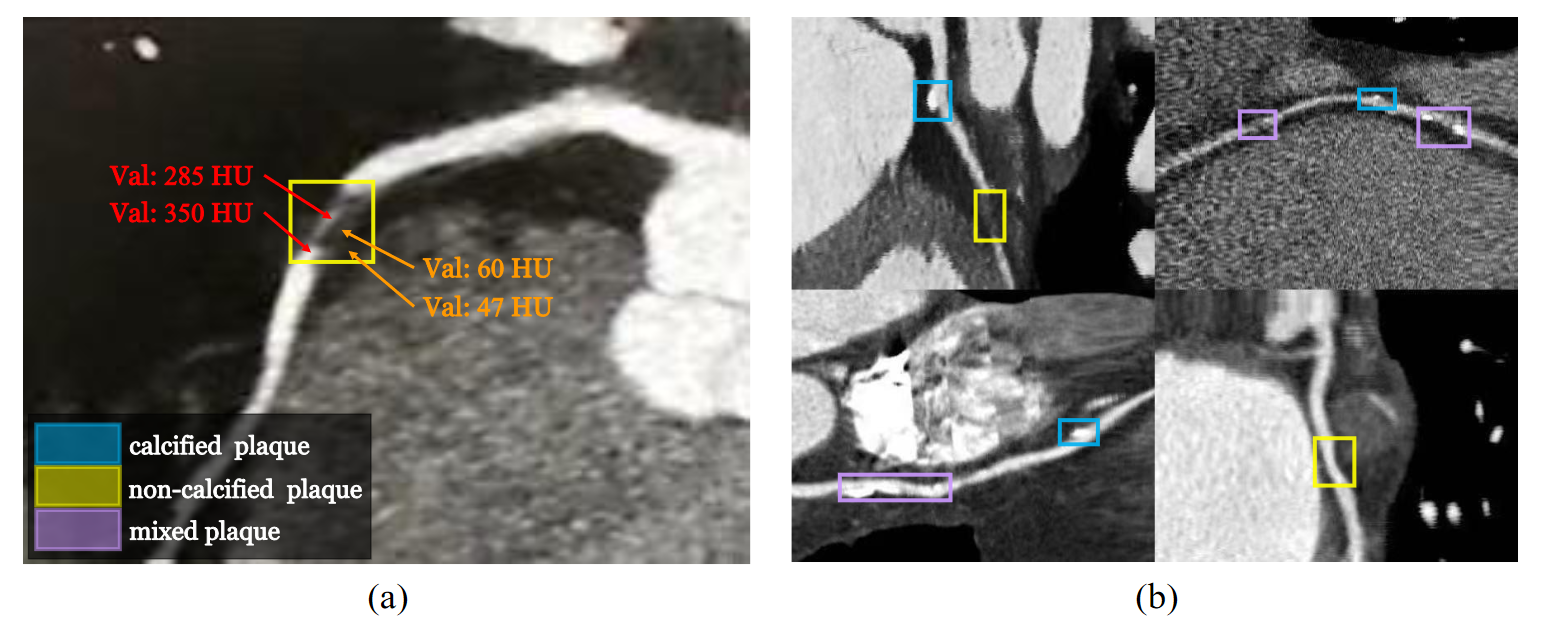

Refer to caption

Figure 1: The HU values of non-calcified plaques are similar to adjacent tissues (a), and types of plaques are complicated and shapes vary from different plaques (b).

In recent years, computer vision technology has been used to detect coronary artery stenosis through CCTA scans of patients to assist clinicians in the diagnosis of CAD. However, it is challenging to realize the automatic diagnosis of CAD, because the contrast of the HU values among adjacent tissues and structures is low. Besides, types of plaques that cause coronary artery stenosis are complicated and there is no shape feature that can be used to strictly describe plaques, as shown in Fig. 1.